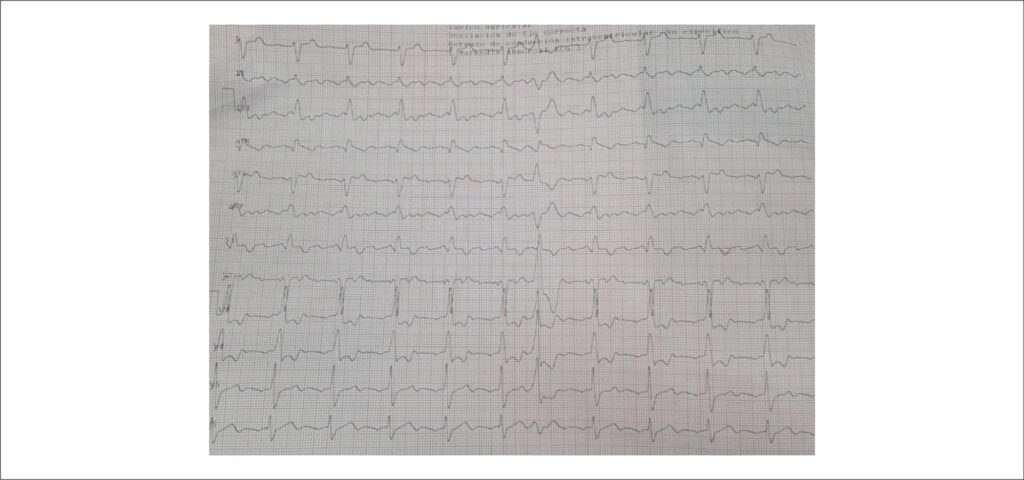

Lutembacher Syndrome Associated With Pulmonary Hypertension: The Importance of Early Diagnosis for Enabling Surgical Treatment

Lutembacher syndrome (LS) is defined by the simultaneous presence of an atrial septal defect (ASD) and mitral stenosis (MS). Although it is a rare condition, its clinical significance lies in the considerable hemodynamic impact and the potential for early progression to irreversible pulmonary hypertension (PH).